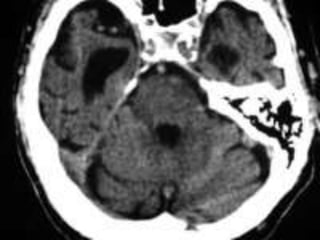

Vascular Insults • SubarachniodHemorrhage. • Lobar and basal ganglia bleeds. • Ischemic strokes. • Venous infarcts. • Disections

Cerebellar infarct withhemorrhagic conversion